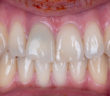

POINT DE CONTACT INTERPROXIMAL EN ZONE ESTHÉTIQUE POINT DE CONTACT INTERPROXIMAL ET ESTHÉTIQUE GINGIVALE EN SECTEUR ANTÉRIEUR L’esthétique gingivale en…